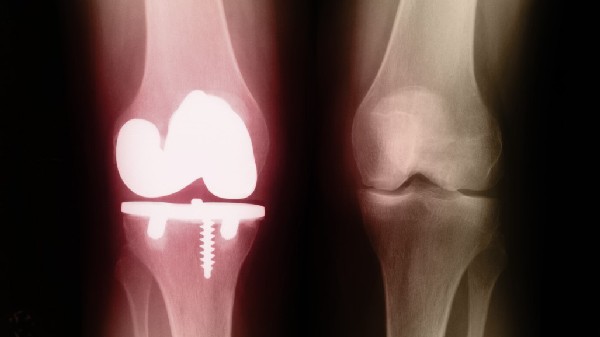

Los tratamientos actuales para la reparación de hueso estructural implican metal poroso, que puede curar mal e infectarse; o un trasplante de hueso de un cadáver, que conlleva un riesgo de enfermedad.